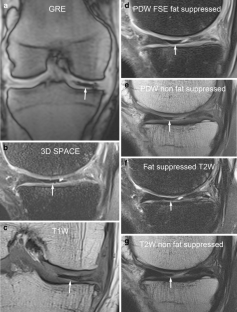

A total of 914 consecutive exams from 875 patients (524 men; mean age, 35 years) were reviewed. Vacuum phenomenon was found in 12 patients (prevalence 1.3%). In six (50%) patients, VP mimicked a meniscal tear, with four cases simulating a torn medial discoid meniscus. The VP signal was not easily differentiated from meniscal signal on most sequences in most cases (9/12). Gradient-recalled echo (GRE) localizer images proved most definitive, with 3D SPACE images the next most effective. Fast spin echo (FSE) images were only occasionally able to differentiate VP from meniscus.

Rarely recognized on MR, VP can mimic meniscal pathology, potentially leading to inappropriate surgery. Because differentiation of VP from the meniscus is challenging on FSE at 3 T, radiologists should become familiar with the appearance of VP and review GRE localizer or 3D images carefully to avoid misinterpretation.